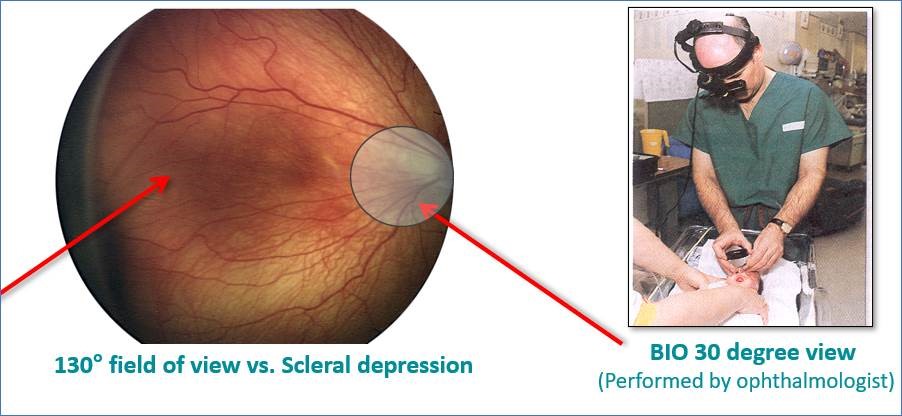

Eines der am häufigsten verwendeten ophthalmischen Instrumente zur Erkennung pädiatrischer Netzhauterkrankungen ist ein binokulares indirektes Ophthalmoskop (BIO). Das BIO wird auf dem Kopf des Ophthalmologen angebracht und bietet diesem eine visuelle Darstellung des Inneren der Augen durch eine Vergrößerungsoptik. Es ermöglicht die Beobachtung der Netzhaut durch Bewegung des BIO-Geräts und der Vergrößerungsoptik, während eine sklerale Depression angewandt wird.16

Eines der am häufigsten verwendeten ophthalmischen Instrumente zur Erkennung pädiatrischer Netzhauterkrankungen ist ein binokulares indirektes Ophthalmoskop (BIO). Das BIO wird auf dem Kopf des Ophthalmologen angebracht und bietet diesem eine visuelle Darstellung des Inneren der Augen durch eine Vergrößerungsoptik. Es ermöglicht die Beobachtung der Netzhaut durch Bewegung des BIO-Geräts und der Vergrößerungsoptik, während eine sklerale Depression angewandt wird.16

Dies ist gewöhnlich ein zeitaufwändiges Verfahren, das den Besuch eines Ophthalmologen vor Ort erforderlich macht. Mithilfe digitaler Augenbildgebung in Kombination mit Telemedizin kann ein effektives und effizientes Screening durchgeführt werden. Darüber hinaus erfordern bestimmte Erkrankungen wie Anopthalmie oder Mikrophthalmie eine externe Bildgebung des Auges zu Dokumentationszwecken, die wiederum auf einfache Weise mithilfe von digitaler Bildgebung durchgeführt werden kann.

Digitale Augenbildgebung zur Erkennung von ROP auf der NICU kann sehr einfach durch geschultes NICU-Personal am Bett eines Babys durchgeführt werden. Hierbei haben sich Systeme wie RetCam bewährt, die ein volles 130 Grad weites Sehfeld bereitstellen, während das BIO nur ein 30-Grad-Sehfeld bietet17. Die Verwendung digitaler Bilder anstelle von basierend auf dem menschlichen Gedächtnis handgezeichneter Dokumentation ermöglicht die objektive Ermittlung des Stadiums und Fortschreitens einer Erkrankung. Zudem verbessert die Fähigkeit zur Weiterleitung von Bildern an andere behandelnde Ärzte zum Einholen einer zweiten Meinung die Genauigkeit von Untersuchungen und Diagnosen.